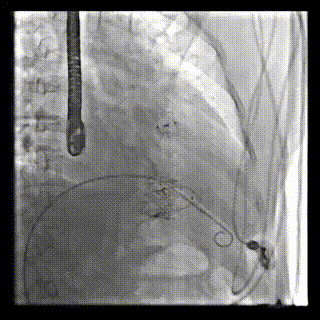

患者二术中DSA

图片